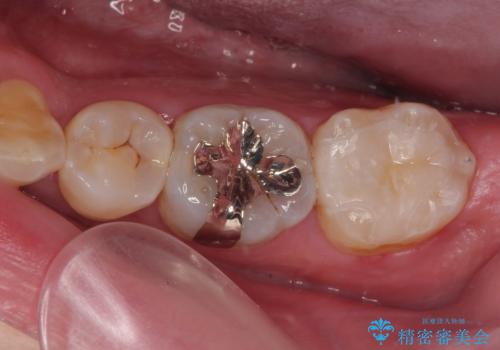

セラミックインレーの装着時には、唾液の侵入を防ぐために、ラバーダム防湿を行いました。

歯と歯の間の虫歯をコンポジットレジンや保険のメタルインレーで治すと段差ができたりして清掃性が悪くなるので、セラミックインレー修復やゴールドインレー修復などの適合の良い詰め物で治療することをオススメします。